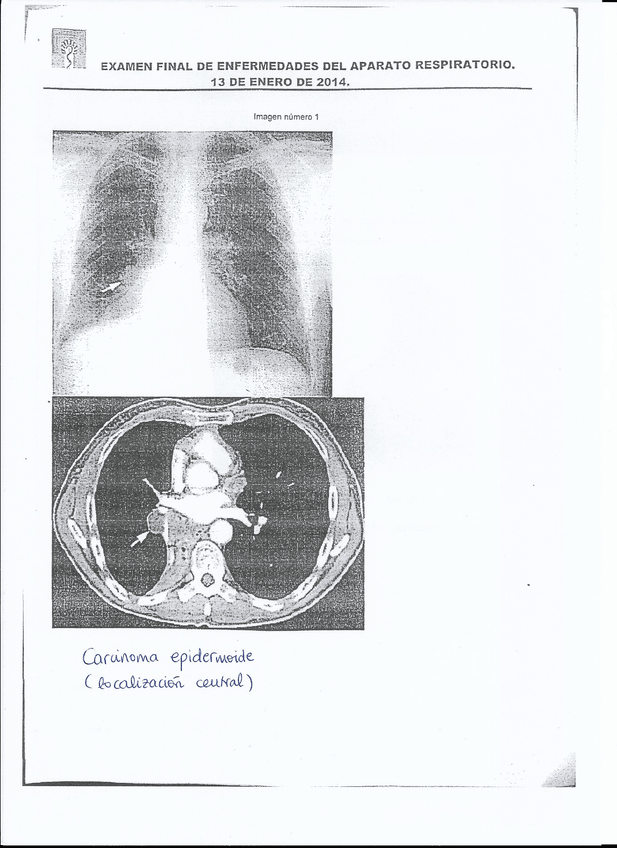

He publicado nuevos examenes de 4º Enfermedades del Aparato Respiratorio: Aparato-Respiratorio_20140113.pdf

10 páginas

He publicado nuevos examenes de 4º Enfermedades del Aparato Respiratorio: EXAMEN Respiratorio - Convocatoria Enero 2014 - CORREGIDO 4.jpg

Imagen

He publicado nuevos examenes de 4º Enfermedades del Aparato Respiratorio: EXAMEN Respiratorio - Convocatoria Enero 2014 - CORREGIDO 1.jpg